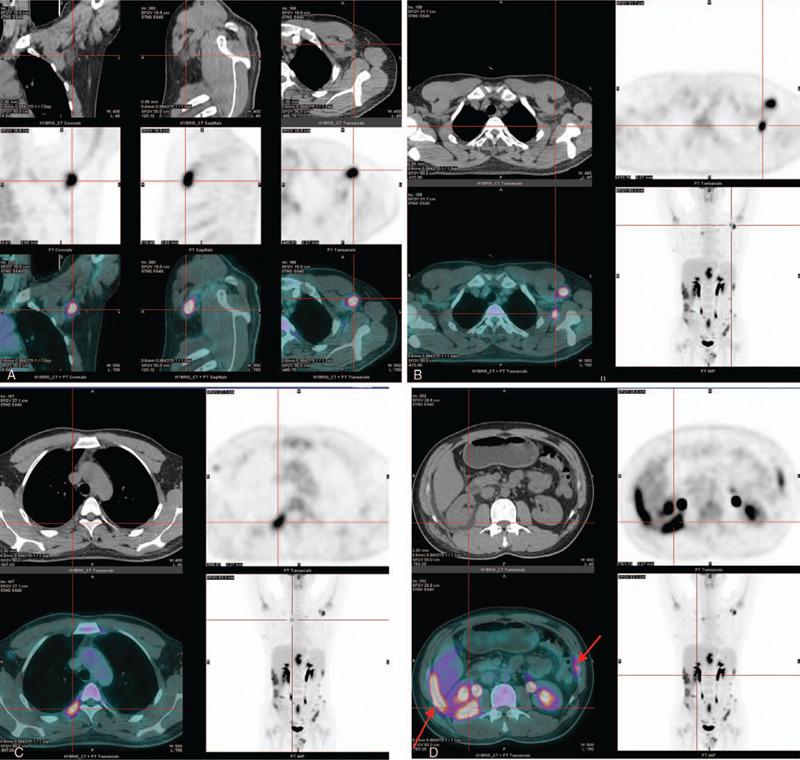

On August 7, 2012, skin biopsy was performed on the lesion of left upper arm of the older twin brother, and then, a diagnosis of subcutaneous panniculitis-like T cell lymphoma (SPTCL) was made. On June 19, 2017, the younger twin brother underwent whole-body fluorine-18 fluorodeoxyglucose positron emission tomography/computed tomography for diagnosis. Soon afterwards, abdominal subcutaneous nodule resection and biopsy was performed on June 28, 2018, and the specimen was diagnosed as SPTCL.

The older twin brother died in March 2015, the younger brother has recovered well and is no longer receiving any treatment LESSONS:: To the best of our knowledge, twin brothers both having this disease has never been previously reported. Moreover, some of the involved areas are also extremely rare detected by fluorine-18 fluorodeoxyglucose positron emission tomography/computed tomography at initial stage. It is beneficial to people to gain some new understanding for SPTCL by this special case and some extremely unusual involved sites in the younger twin brother.

2012年8月7日,对年长双胞胎兄弟的左上臂病变进行皮肤活检,随后诊断为皮下脂膜炎样T细胞淋巴瘤(SPTCL)。2017年6月19日,年幼的双胞胎兄弟接受全身氟-18氟脱氧葡萄糖正电子发射断层扫描/计算机断层扫描以进行诊断。此后不久,于2018年6月28日进行腹部皮下结节切除及活检,标本诊断为SPTCL。

据我们所知,此前从未报道过双胞胎兄弟均患此病的情况。此外,一些受累部位在疾病初期通过氟-18氟脱氧葡萄糖正电子发射断层扫描/计算机断层扫描检测到也极为罕见。通过这个特殊病例以及年幼双胞胎兄弟一些极其不寻常的受累部位,有助于人们对SPTCL获得一些新的认识。